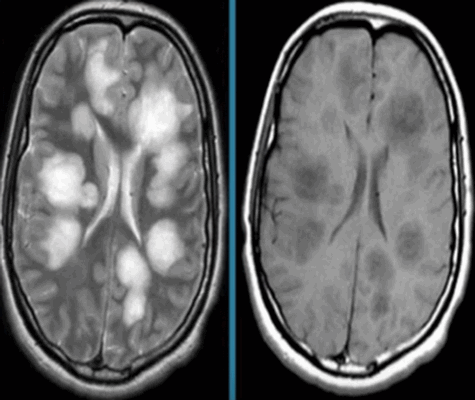

Острый рассеянный энцефаломиелит на МРТ

Если при МРТ головного мозга выявлены очаги, их расценивают как симптомы патологии органа. Зоны гипер- или гипоинтенсивного МР-сигнала свидетельствуют о нарушении структуры определенного участка церебрального вещества. Очаговые изменения могут быть единичными или множественными, крупными, мелкими, диффузными и т.п.. Подобное наблюдается при:

- рассеянном склерозе или иных демиелинизирующих заболеваниях; , Пика, Паркинсона и т.п.;

- энцефаломиелите и других заболеваниях.

Очаговые изменения могут быть результатом некроза, гнойных процессов, ишемии, воспаления тканей, разрушения нервных волокон и т.п. Фокальная патология на МР-сканах почти всегда свидетельствует о развитии серьезного заболевания, а в некоторых случаях указывает на опасность для жизни больного.